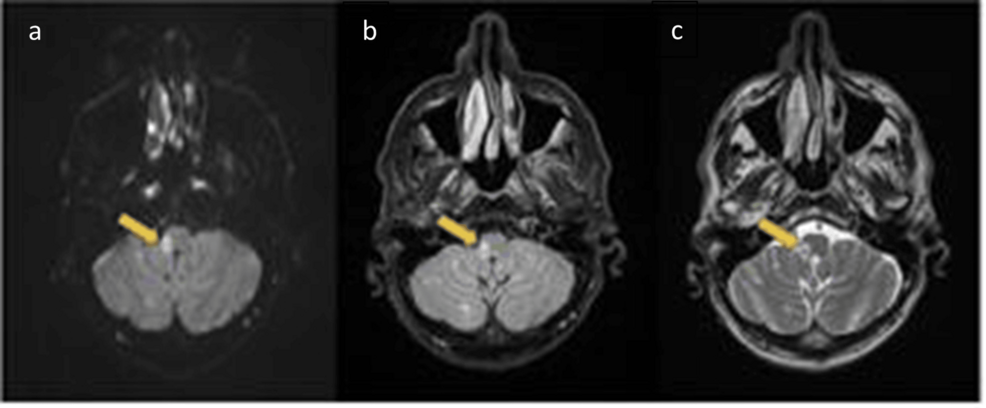

Un reciente estudio de casos presentado en Cureus destaca la importancia de considerar diferentes causas al diagnosticar el síndrome de Wallenberg. Este síndrome, también conocido como síndrome lateral medular, se produce por una interrupción del flujo sanguíneo al tronco encefálico.

El estudio presenta dos casos individuales. En el primero, se identificó una disección de la arteria vertebral como la causa del síndrome de Wallenberg. Una disección de la arteria vertebral implica un desgarro en la pared de la arteria, lo que puede restringir el flujo sanguíneo. El segundo caso reveló que la trombofilia, una predisposición a la formación de coágulos sanguíneos, fue la etiología subyacente.